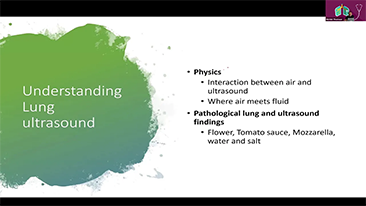

Moins de stĂŠthoscope, plus d'ĂŠchographie??